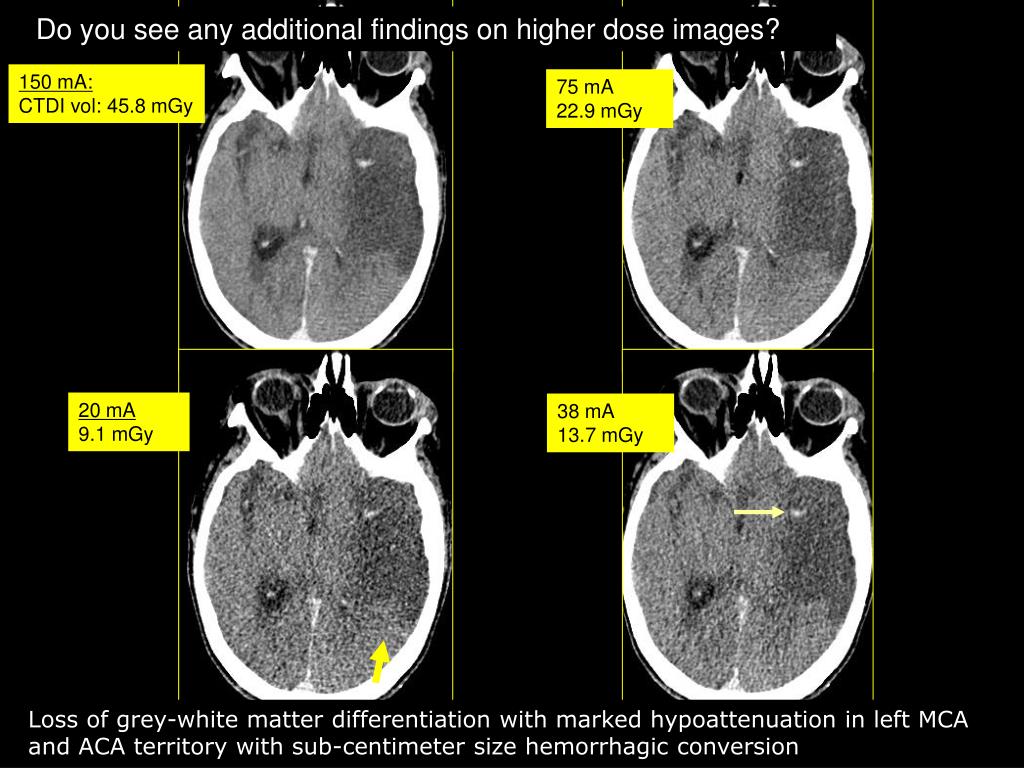

16. Do you see severe hypo attenuation in lt MCA and ACA with multiple foci of sub cm hemorrhagic conversion

17. Do you see any additional findings on higher dose images? 150 mA: CTDI vol: 45.8 mGy 75 mA 22.9 mGy 20 mA 9.1 mGy 38 mA 13.7 mGy Loss of grey-white matter differentiation with marked hypoattenuation in left MCA and ACA territory with sub-centimeter size hemorrhagic conversion